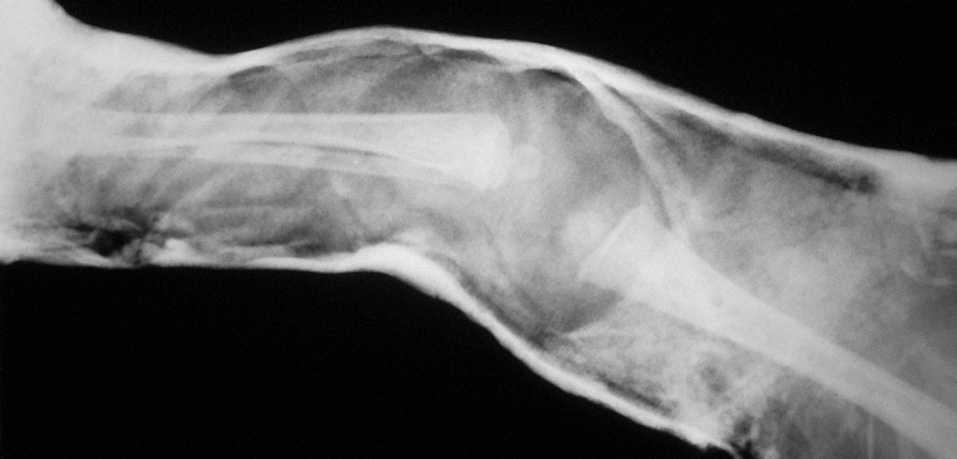

La luxación congénita de rodilla (LCR) es un proceso raro, siendo 100 veces menos frecuente que la de cadera (LCC) y hay mayor incidencia en el sexo femenino. Fue en 1822 cuando Chatelaine describió el primer caso de LCR. Se distinguen tres grupos según la clasificación de Ferris1 , basada en criterios clínicos y radiológicos: Tipo I o recurvatum severo de la rodilla, estando ésta hiperextendida más de 15°, con un rango de flexión completo y sin alteraciones radiológicas. Tipo II o subluxación de la tibia sobre el fémur, rodilla hiperextendida más de 15°, con alguna restricción para la flexión y radiológicamente subluxada. Tipo III

o luxación completa, con una rodilla inestable, radiológicamente luxada, y un rango de movilidad variable.

MATERIAL Y MÉTODOEntre los años 1990 y 2000, 16 pacientes (27 rodillas) fueron diagnosticados y tratados de LCR en nuestro centro (tabla 1). Once niñas (69%) y 5 niños (31%). El período de seguimiento medio fue de 5 (1,5-16) años. En 11 casos la LCR fue bilateral y en 5 unilateral, 3 izquierdas y 2 derechas. Según la clasificación de Ferris y Aichroth1 , las luxaciones congénitas se dividen en tres grupos. En nuestra serie, 4 rodillas (15%) pertenecían al tipo I o recurvatum ; 5 (19%) se englobaban en el tipo II o subluxación; las restantes 18 (66%) eran del tipo III o luxación completa (fig. 1). En relación al embarazo, 12 pacientes (75%) fueron a término y 4 (25%) fueron prematuros. Un embarazo fue gemelar. El parto fue vaginal en 8 niños (50%) y con cesárea en los otros 8 (50%). La presentación cefálica fue la más frecuente, 8 casos (50%), seguida de la podálica y de nalgas con 4 (25%) cada una.

La mayoría de los casos, 10 pacientes, 16 rodillas (63%) fueron diagnosticados y tratados en las primeras 24 horas de vida. Se trata de realizar una tracción manual suave pero intensa, desplazando anteriormente el 1/3 distal fe-moral y a posterior el 1/3 proximal de tibia, corrigiendo la luxación. Se considera la luxación reducida cuando se consigue una flexión de más de 85°-90°, con confirmación radiológica. Es entonces cuando se coloca un yeso manteniendo la posición. Dicha inmovilización es cambiada cada dos semanas. Esta reducción inmediata se logró en 4 de 10 pacientes (6 rodillas) (23% de las rodillas). En los restantes 6 pacientes (10 rodillas) se apreció una resistencia a la flexión con una contractura cuadricipital que impedía la reducción (fig. 2). Entonces se usaron yesos seriados con diferentes grados de flexión en función de la tolerancia de las partes blandas; dichas escayolas eran cambiadas semanalmente, progresando en los grados de flexión. La duración media de la inmovilización con yeso en ambos grupos fue de 90 (42150) días. Del total de las 16 rodillas diagnosticadas y tratadas en las primeras 24 horas, únicamente una (6%) precisó tratamiento quirúrgico. Consistió en una liberación de la cintilla iliotibial.

Figura 1. Luxación congénita de rodilla tipo III de Ferris.